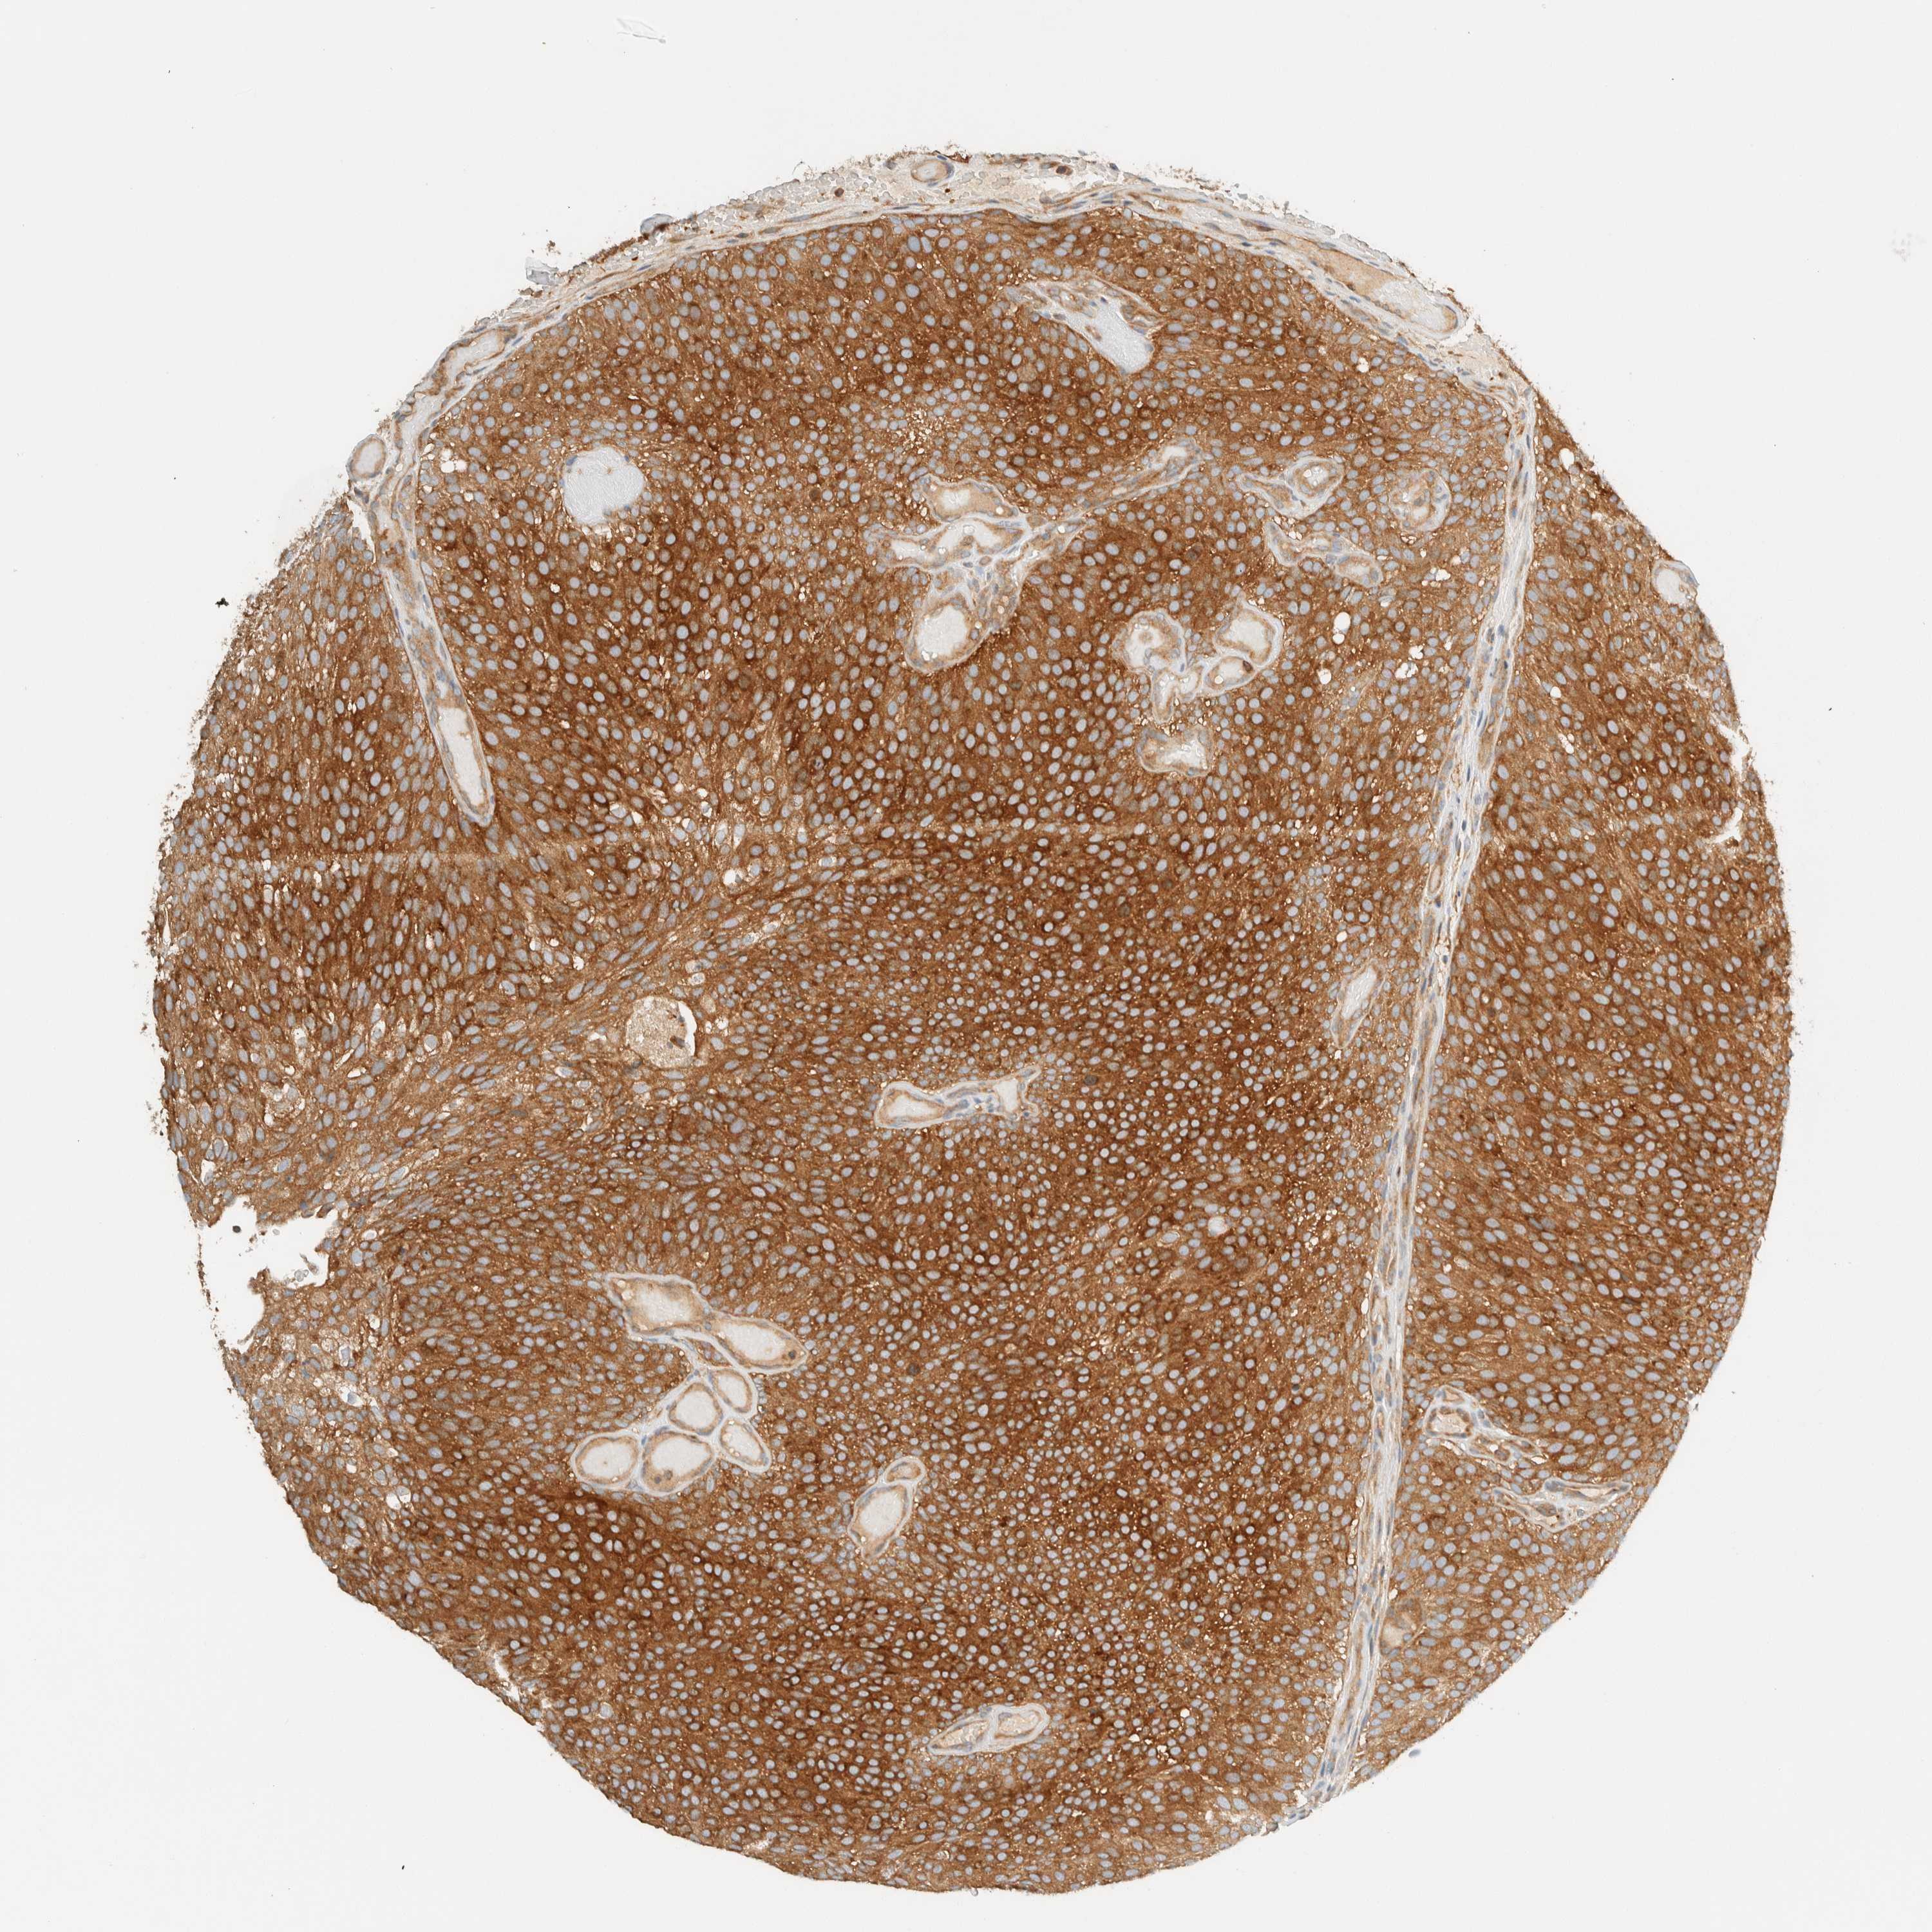

UROTHELIAL CANCER - Protein expressioni

A mouse-over function shows sample information and annotation data. Click on an image to view it in a full screen mode. Samples can be filtered based on level of antibody staining by selecting one or several of the following categories: high, medium, low and not detected. The assay and annotation is described here.

Note that samples used for immunohistochemistry by the Human Protein Atlas do not correspond to samples in the TCGA dataset.

Antibody stainingi

Antibody staining in the annotated cell types in the current human tissue is reported as not detected, low, medium, or high, based on conventional immunohistochemistry profiling in selected tissues. This score is based on the combination of the staining intensity and fraction of stained cells.

Each image is clickable and will lead to virtual microscopy that enables deeper exploration of all samples and also displays staining intensity scores, fraction scores and subcellular localization as well as patient and tissue information for each sample.

Antibody HPA023399

Antibody HPA023822

Urothelial carcinoma, Low grade

Urothelial carcinoma, High grade